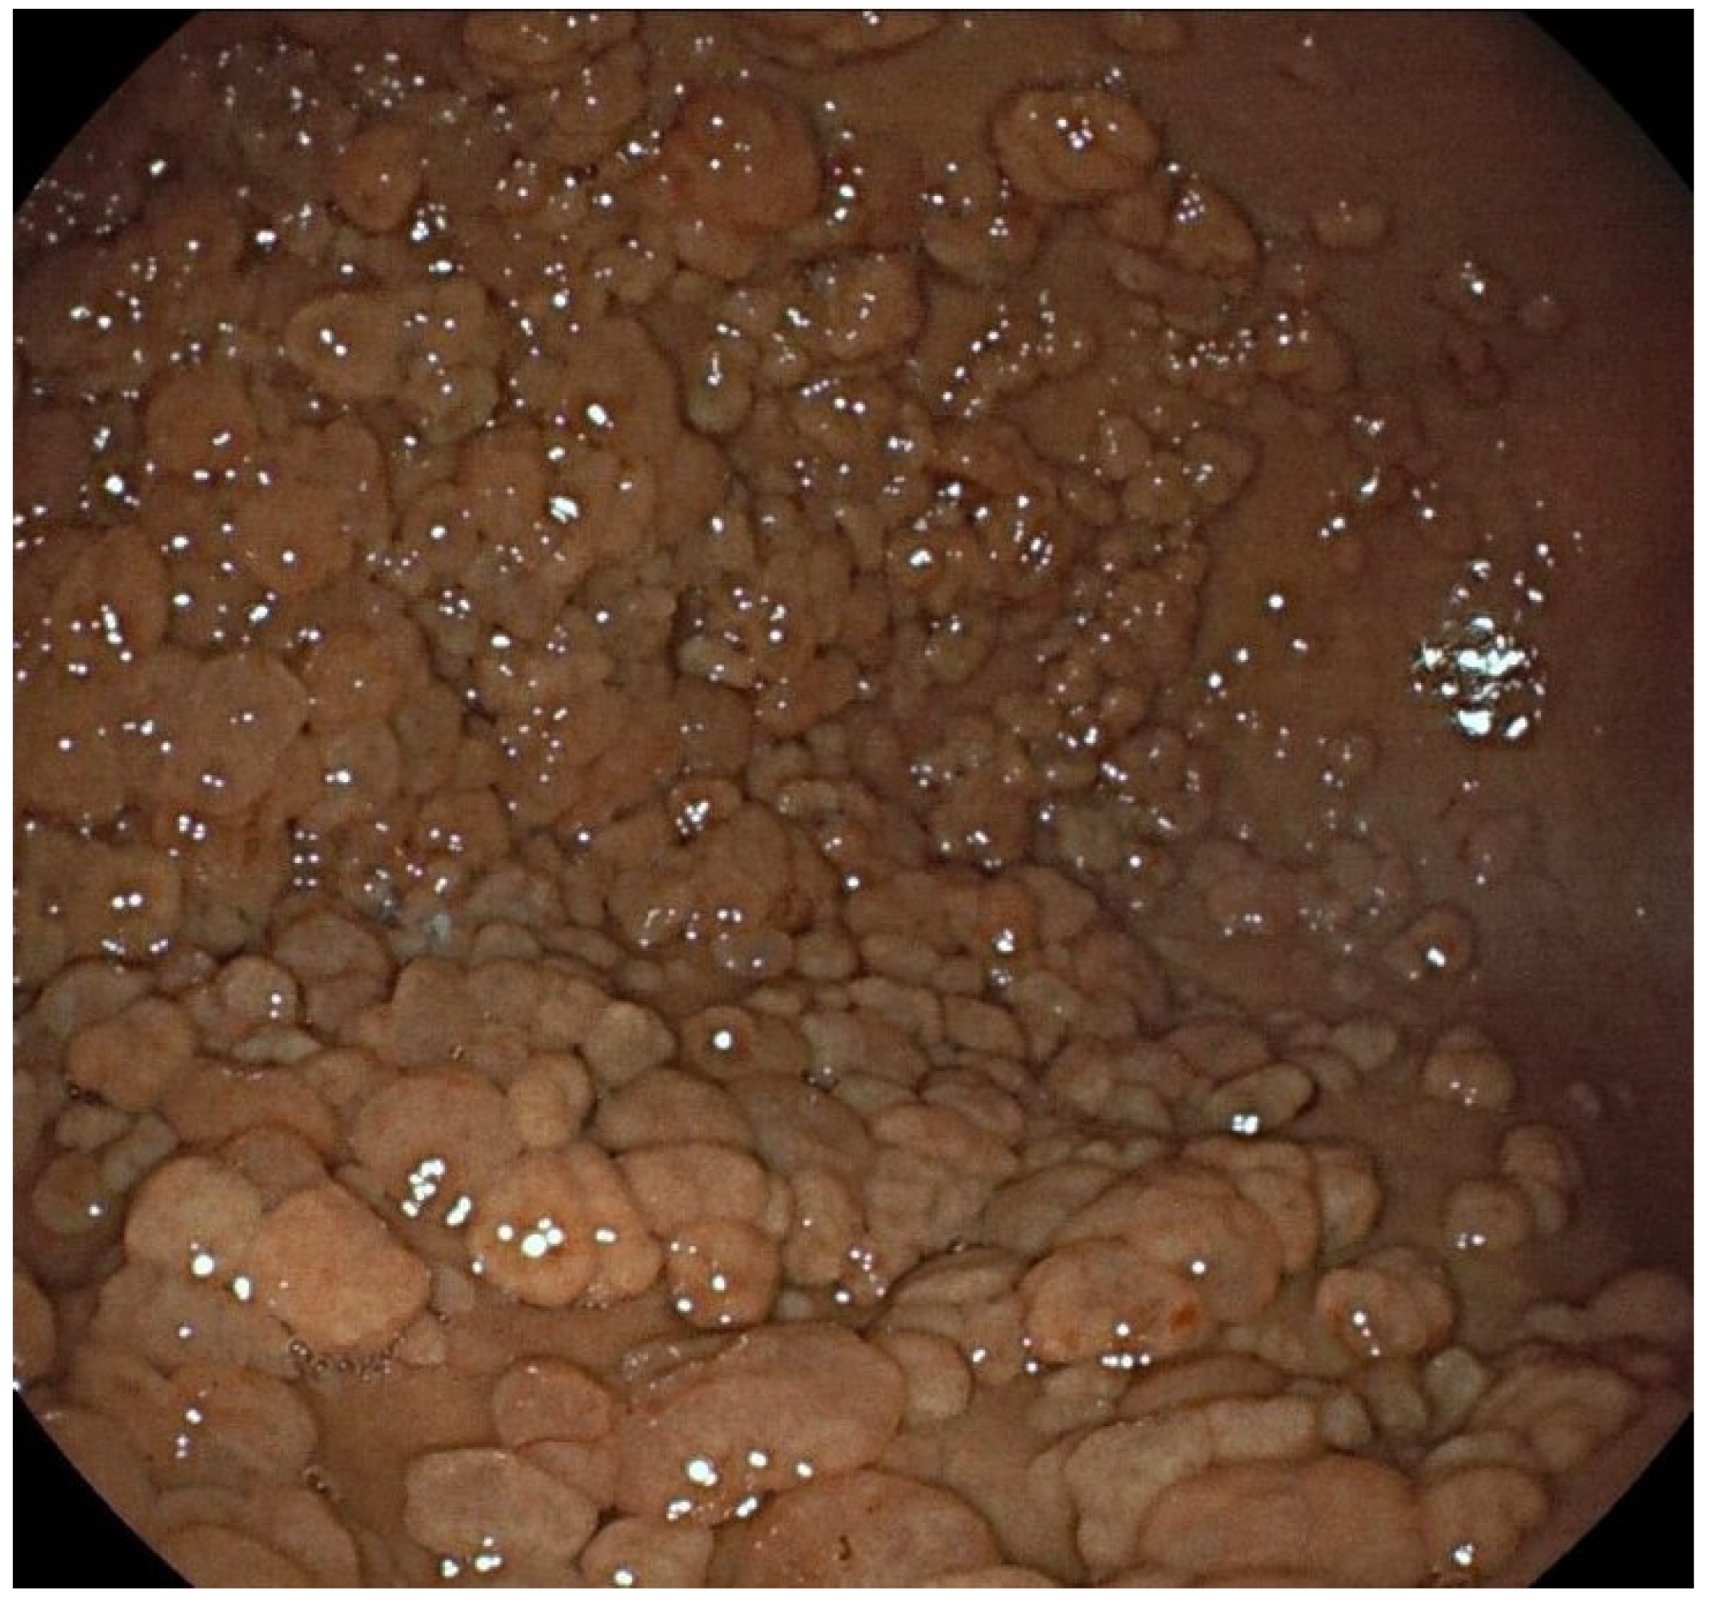

Figure 2. White light endoscopic (WLE) image: numerous fundic gland polyps in a “carpet” distribution in a patient with familial adenomatous polyposis. Images were provided by Dr. María Daca.

It is estimated that up to 25% of sporadic cases may present multiple polyps. In cases associated with hereditary syndromes, between 40 and 80% of patients with FAP and the majority of patients with GAPPS can present more than 100 polyps (Figure 2) [8]. The simultaneous presence of duodenal adenomas should alert to the possibility of FAP or MAP [25,26].

In a minority, FGPs are associated with polyposis syndromes, such as familial adenomatous polyposis (FAP), MUTYH-associated polyposis (MAP) and gastric proximal adenocarcinoma and polyposis syndrome (GAPPS). In the syndromic context, the polyps are numerous, sometimes with a “carpet” distribution, with an earlier presentation (between 20 and 40 years) and without sex predominance [8].